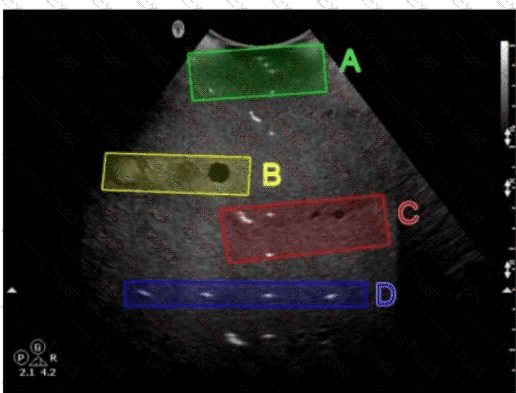

Which target group in this image of a tissue-mimicking phantom is used to evaluate axial resolution?

Options:

A.

Option A

B.

Option B

C.

Option C

D.

Option D